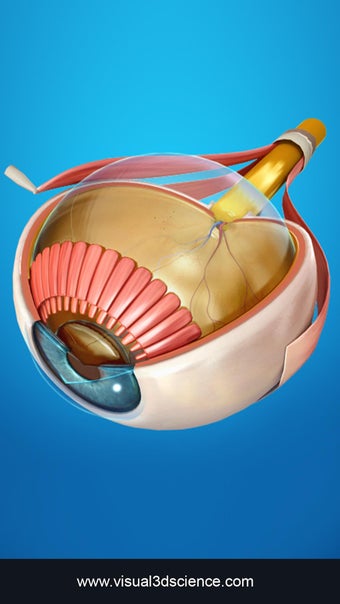

Изучите в деталях человеческий глаз и его анатомию с помощью этого простого в использовании бесплатного приложения для Android. Он позволяет масштабировать и вращать на 360° вокруг высокореалистичной 3D-модели глаза, а также рисовать на экране или прослушивать звуковое произношение каждого термина.

Вы можете выбрать X- просмотр луча, скрытие и отображение отдельных частей глаза, а также рисование или белый цвет на экране и обмен снимками экрана, звуковое произношение для всех анатомических терминов и многое другое.

Каждая часть разделена на отдельный вид, где вы можете можно увидеть название детали и ее расположение на глаз.